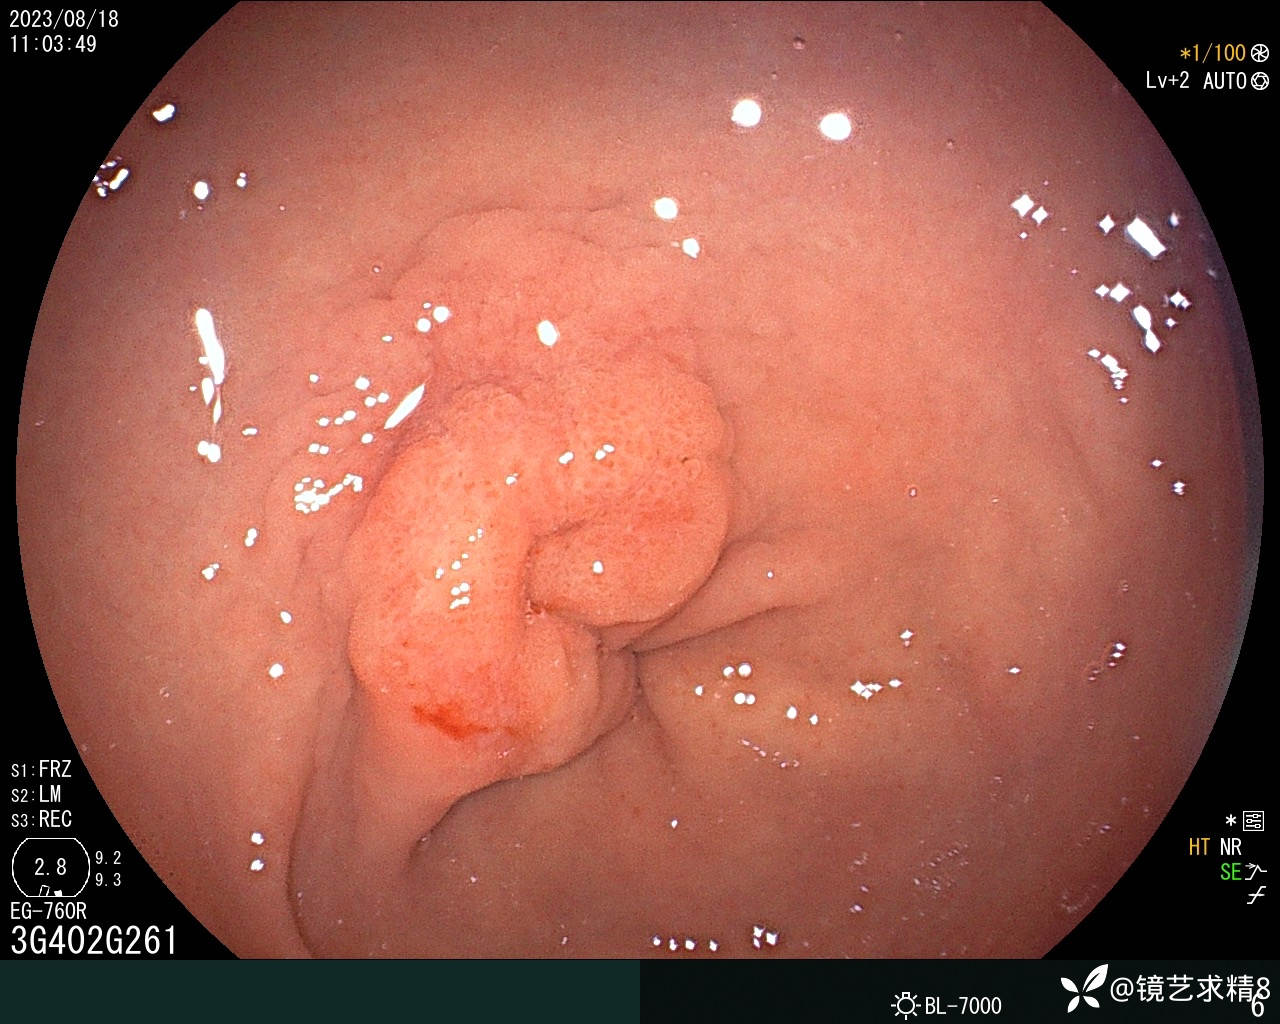

胃窦:黏膜红白相间,前壁与小弯侧交界近幽门见一0-Ia+IIc型病变,约20*30mm大小,BLI染色局部呈淡茶色,边界可见,表面结构欠规则,取病检2块+HP检查,质软。

内镜下诊断:1. 胃窦0-Ia+Ic型病变,不除外早期ca?请结合病检+HP检查